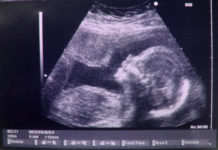

গর্ভের সন্তান ছেলে না মেয়ে জানতে পরীক্ষা করানো কেন অবৈধ নয়: হাইকোর্ট

মাতৃগর্ভে

থাকা শিশু ছেলে না মেয়ে সেটা জানার জন্যে পরীক্ষা (আলট্রাসনোগ্রাফ) করানো এবং তার

ফলাফল প্রকাশ করাকে কেন অবৈধ এবং বেআইনি ঘোষণা করা হবেনা, তা জানতে...